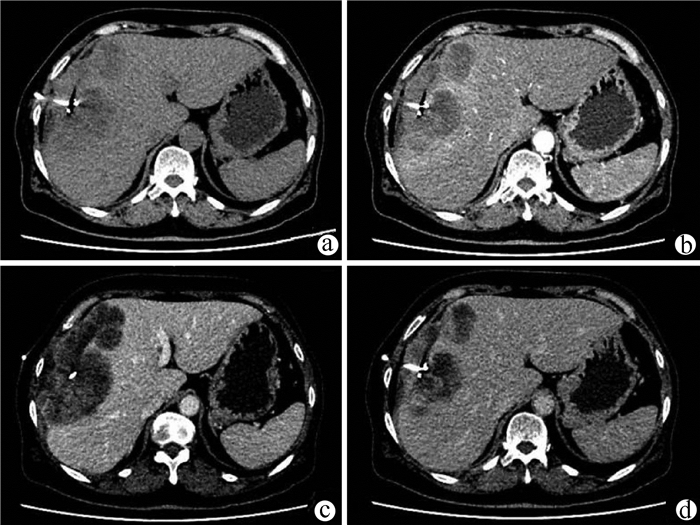

Primary splenic Kaposi sarcoma: A case report

Youchun LI, Guichao XU, Wenlei QI

2021, 37(7): 1668-1669. DOI: 10.3969/j.issn.1001-5256.2021.07.038

Abstract(727) HTML (199) PDF (2767KB)(19)

Abstract: